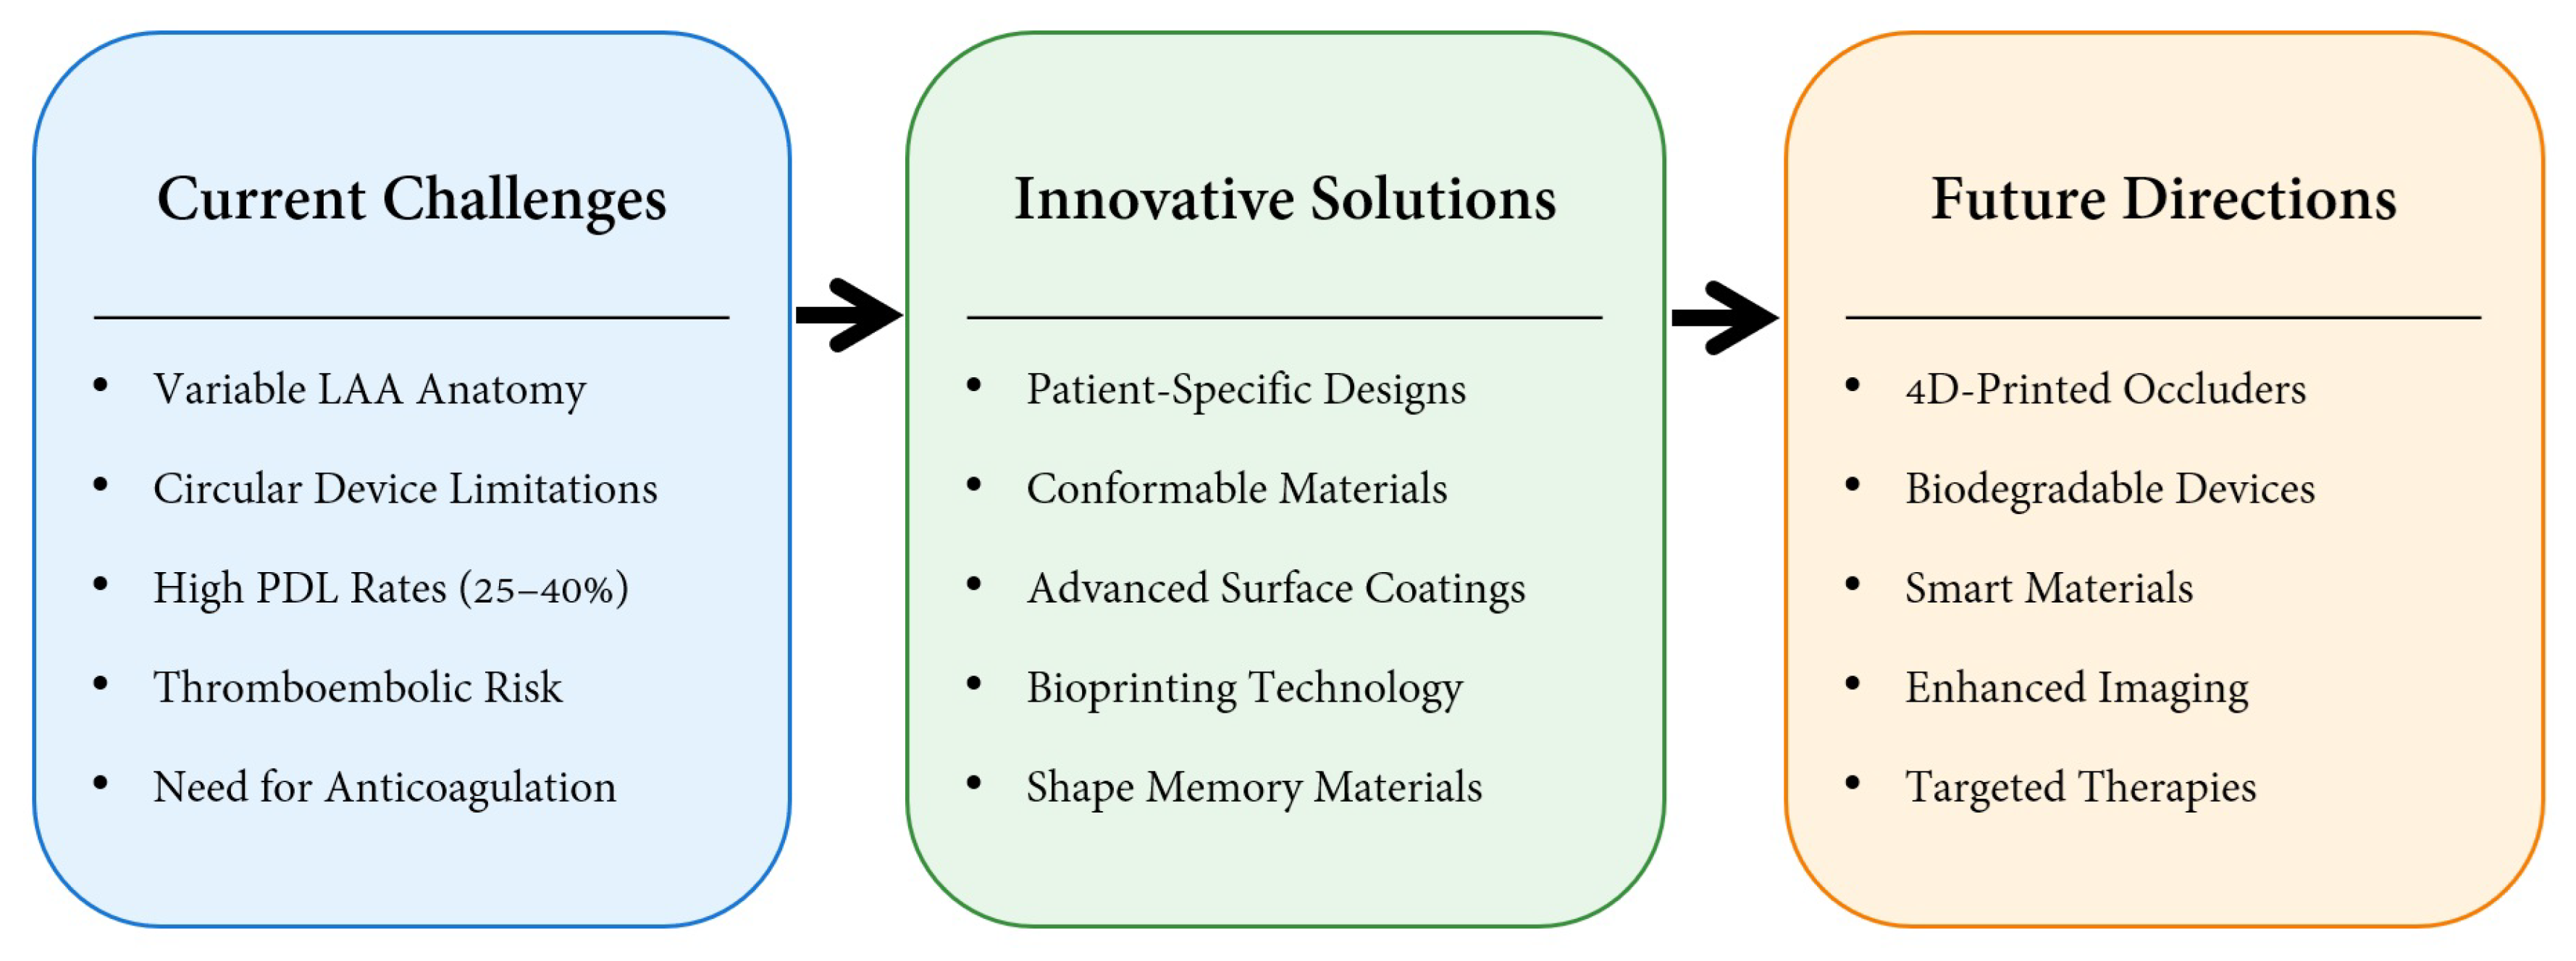

3. Discussion

3.1. Surface Modification

3.2. Upconversion 3D Bioprinting

3.3. Patient-Specific Occluder

3.4. Shape Memory Biodegradable

3.5. Bio-Inspired Absorbable

4. Conclusions